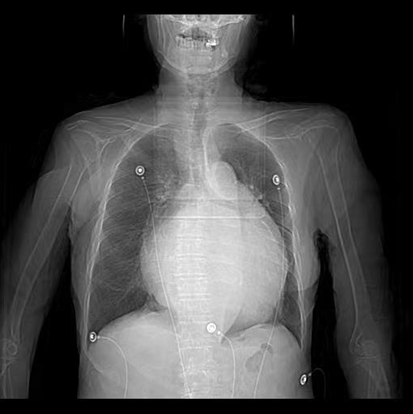

图一:患者胸片显示心影显著增大,以左心房增大为主

患者因“发作性气短20余年”之主诉入院,多次心脏超声诊断为风湿性心脏瓣膜病二尖瓣狭窄,此次因症状再发加重入院。经评估患者二尖瓣瓣口面积为0.67cm2,二尖瓣跨瓣压差为22mmHg,左房前后径94mm,左右径109mm,为重度风湿性二尖瓣狭窄伴罕见巨大左心房。在心内二科主任寿锡凌带领下,全科室充分讨论。因患者年龄大、基础情况差、无法耐受外科手术治疗,药物治疗不能解除瓣膜狭窄,只能选择经皮二尖瓣球囊扩张成形术。但鉴于患者巨大左心房已使心脏结构发生了巨大变化,单纯通过传统DSA影像结合经胸心脏超声指引下穿刺房间隔引起心脏破裂、心脏填塞、房间隔穿刺部位不佳影响手术操作、二尖瓣狭窄严重难以寻找二尖瓣瓣口、球囊扩张时球囊扩张位置不佳、术中难以即刻评估瓣膜扩张效果等均会导致手术失败进而威胁患者生命。考虑到心腔内超声宛如“心腔内的眼睛”可实时为术者提供心腔内的解剖结构毗邻关系,弥补传统DSA影像结合经胸心脏超声的不足,能为术者决策实时提供指导,确保手术能够安全、准确、顺利完成,最终决定为患者行心腔内超声指引下经皮二尖瓣球囊扩张成形手术。

此例手术由姚晓伟主任医师、韩稳琦主治医师、赵永勇主治医师通过心腔内超声指导下进行,通过心腔内超声精准构建心脏模型、直视下穿刺房间隔,后通过心腔内超声及左心房造影寻找狭窄的二尖瓣瓣口,并指引二尖瓣球囊扩张导管顺利经狭窄的二尖瓣口至左心室,在心腔内超声的指引下选择最佳位置以26mm球囊导管反复扩张狭窄的二尖瓣。术后第二天复查心脏超声,患者二尖瓣瓣口面积由术前0.67cm2扩大到术后1.69cm2,二尖瓣跨瓣压差由术前22mmHg降低至术后的16mmHg,左房前后径由术前94mm减小至术后92mm,左房左右径由术前109mm减小至术后102mm,并且球囊扩张后未引起明显的二尖瓣反流,患者心功能明显改善,自觉症状明显好转出院。